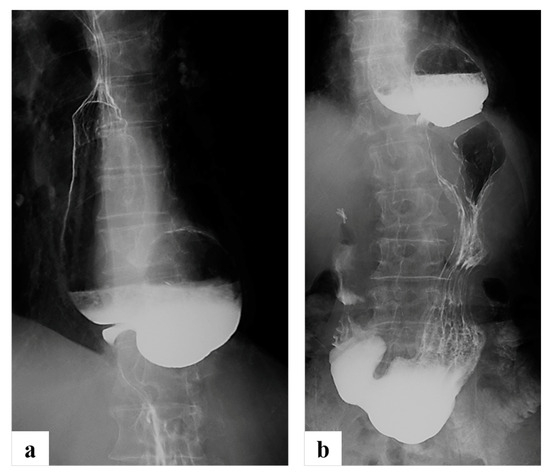

2.1. Case Presentation